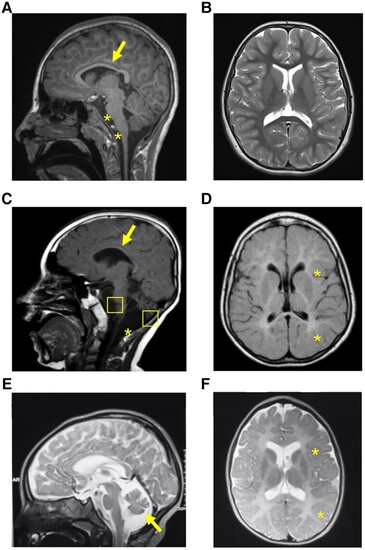

MRI sections of the brain of the three probands harbouring biallelic PTMT1 variants. (A) T1 sequence, sagittal view. Evidence of thin corpus callosum (arrow), atrophy of pons and medulla (star). (B) T2 sequence, axial view. No white or grey matter changes were observed. (C) T1 sequence, sagittal view, showing hypoplasia of corpus callosum (arrow), cerebellar and brainstem atrophy (squares), and mega cisterna magna anomaly (asterisk). (D) T1 sequence, axial view, showing supratentorial white matter signal hyperintensity in keeping with hypomyelination. (E) T2 sequence, sagittal view, showing diffuse cortical atrophy, and cerebellar atrophy (arrow). (F) T2 sequence, axial view, showing areas of hypomyelination.